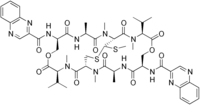

Echinomycin is a peptide antibiotic. It is a dimer of two peptides creating a cyclic structure. It contains a bicyclic aromatic chromophore that is attached to the dimerized cyclic peptide core and a thioacetal bridge. It intercalates into DNA at two specific sites, thereby blocking the binding of hypoxia inducible factor 1 alpha (HIF1alpha).[1]